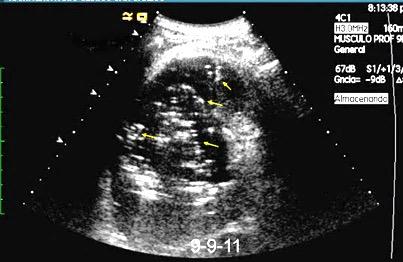

Patrón ecográfico de empiema

Anecoico.....0%. (0 de 47)

Complejo no septado no hiperecoico... ……………..0% (0 de 36)

Complejo, no septado hiperecoico......100% (2/2)

Complejo septado …35% (11 de 31)

Ecogénico homogéneo .... 100% (2 de 2)

Wang T et al. Value of ultrasonography in determining the nature of pleural effusion. Analysis of 582 cases. Medicine 2022.

Chih-Yen Tu et al. Chest Ultrasound Study Pleural Effusions in Febrile Medical ICU. Chest 2004